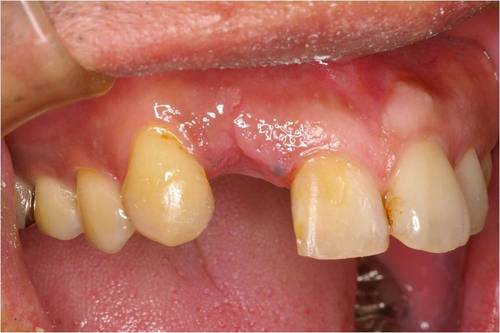

しっかり骨の中に埋められています。